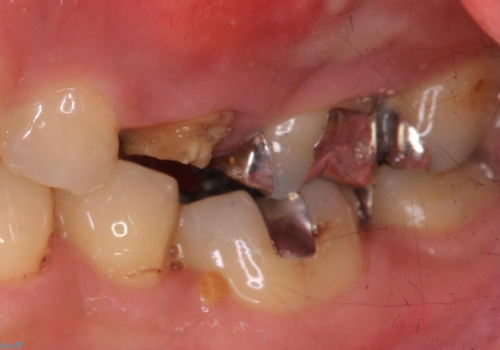

歯茎が腫れる インプラントでの治療

- 40代女性

- 10ヶ月

- 左上5/インプラント:242,000円 骨増生:55,000円 カスタムアバットメント:110,000円 インプラント用仮歯:22,000円 ジルコニアクラウン:121,000円 合計550,000円費用は治療当時の料金となります